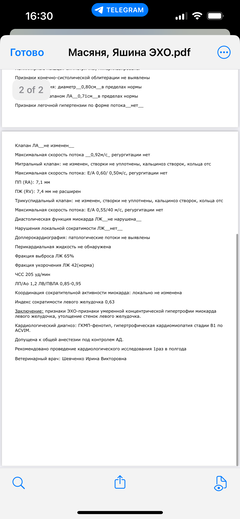

Ярко выраженная болезненность в области крестца, на обезболе полегче. По результатам приема невролога проведена миелография - множественная компрессия, возможно опухоль, возможно грыжа, нужно удалять...